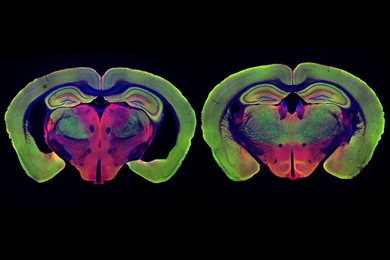

Reporting for BBC Future, David Robson spotlights Prof. Li-Huei Tsai’s work developing a new non-invasive treatment that could potentially alleviate symptoms of dementia using a combination of flashing and clicking lights. Robson writes that Tsai’s research “represents a radical new approach to preventing and treating the most common form of dementia.”